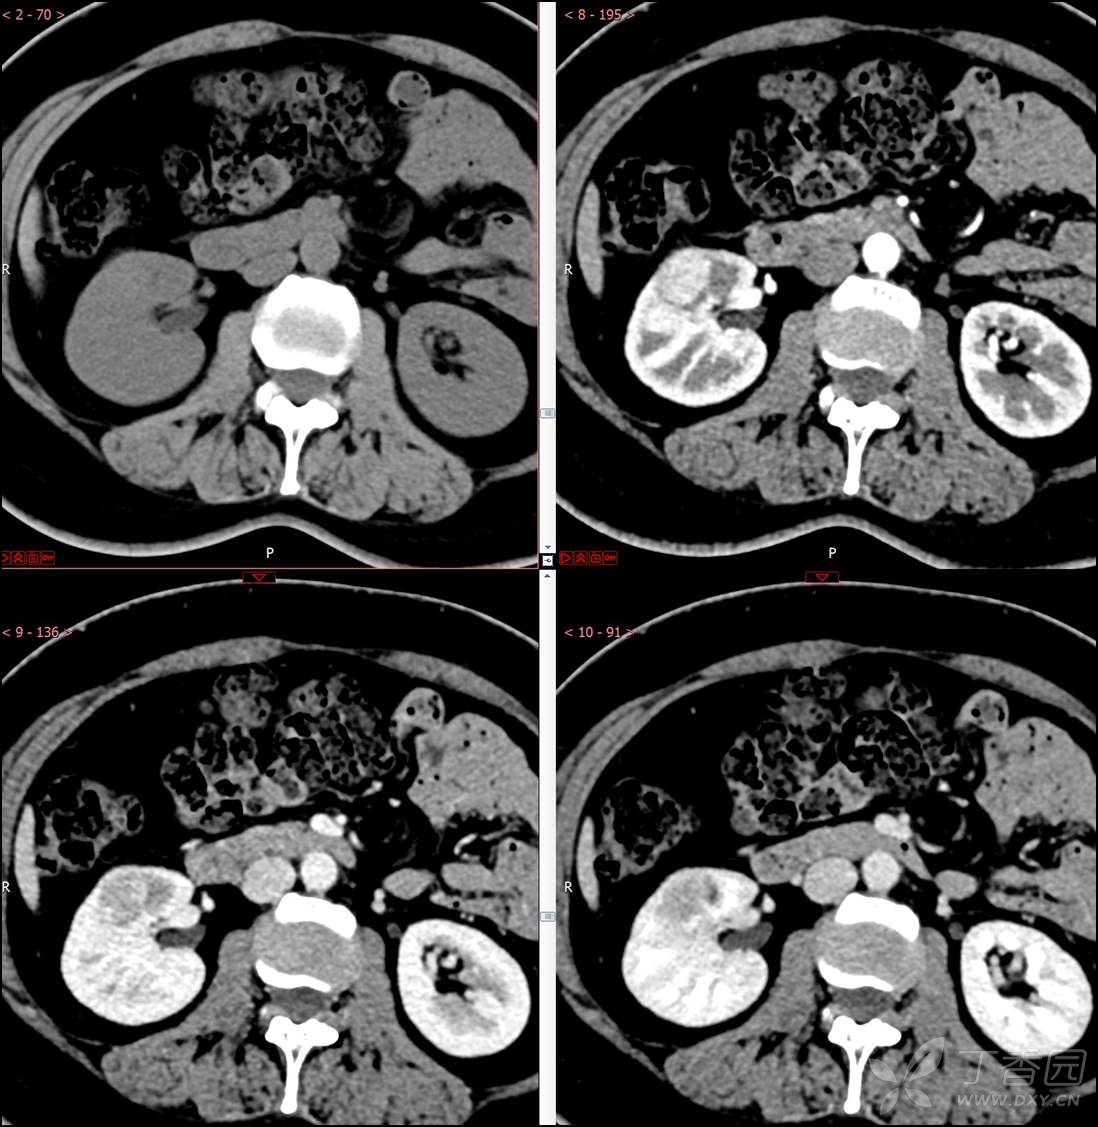

【影诊笔记516】中年女性,检查发现肾占位2周就诊~『嗜酸细胞腺瘤』

主诉:检查发现肾占位2周

简要病史:患者2周前体检发现肾实质性占位,无腰痛,无血尿,无尿频、尿急、尿痛,无发热,在外未行特殊治疗。患者为行进一步治疗就诊于我院,门诊以“肾占位性病变 ”收入我科,患者自发病以来,神志清,精神可,小便如上所述,大便正常,体重无显著变化。